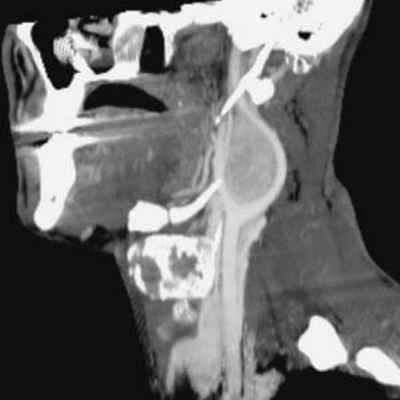

Пациентка 37 лет, обратилась для исследования шейного отдела позвоночника, с жалобами на головные боли, боли в шее, осиплость голоса, которая усиливалась на протяжении последних 6 месяцев. Обследование проводилось на магнитно-резонансном томографе фирмы Toshiba мощностью 1,5 тесла.

При проведении исследования шейного отдела позвоночника, было выявлено в области яремного отверстия справа образование, с признаками масс-эффекта, вызывающее деформацию внутренней сонной артерии и луковицы яремной вены; имеющего гиперинтенсивный сигнал в режиме Т2 ВИ и Flair изоинтенсивный сигнал на Т1 ВИ, в режиме DWI ограничения диффузии не определялось.

Размеры образования 15,2х17,4х18,6 мм. После внутривенного введения контрастирующего вещества («Гадовист» — 15 мл) отмечалось его интенсивное накопление.

Также отмечалась правосторонняя асимметрия гортани, ее деформирование, за счет пластинки перстневидного хряща и голосовой мышцы.

Объемное образование краниобазальной области справа параганглиома.

В дальнейшем, при проведении оперативного лечения и гистологического исследования, диагноз был подтвержден.